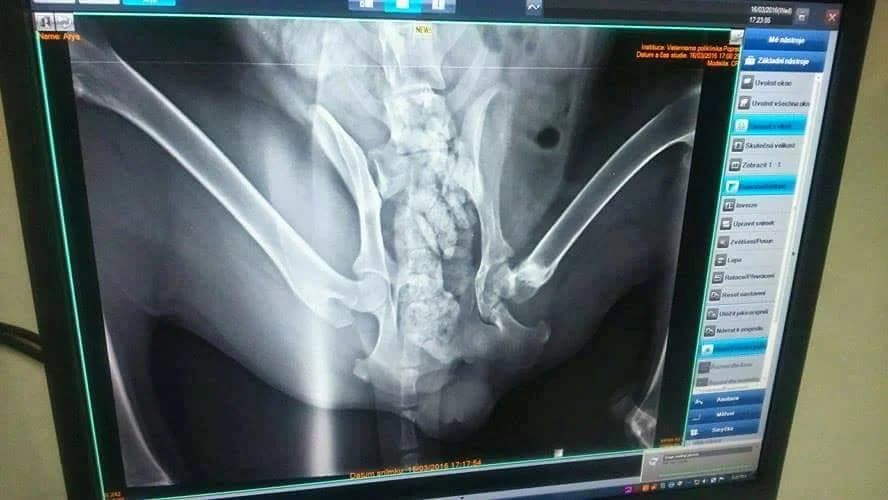

NOVE INFO (23.5.2016): Prinášame Vám nové informácie o krásnej fenke Aryi, ktorá sa našla vyhodená na ulici s mesiac a pol starou zlomeninou bedrového kĺbu. Práve dnes ubehli dva mesiace od operácie,ktorú podstúpila Arya hneď po príchode do útulku. Zabojovala a dnes s hrdosťou a krásnym pocitom na duši môžeme prehlásiť:, ARYA JE ZDRAVÝ PES. UŽÍVA SI KAŽDÚ PRECHÁDZKU A NAJRADŠEJ ZO VŠETKÉHO SA NAHÁŇA. POUŽÍVA VŠETKY ŠTYRI LABKY . “ Áno čítate správne. Po chorom, vychudnutom psovi,kt. dlhé týždne nepoužíval jednu labku nie je ani stopy. Arya je povahovo dokonalá fenka a v útulku čaká na milujúci domov 🙂 Jedného rána dostala mestská polícia hlásenie o fenke, ktorá sa splašene ťahá o troch nohách po Kvetnici. Odchytili ju a doniesli do útulku. Aj napriek plnému stavu sme ju museli prijať. Povedať nie takémuto prípadu? Srdce by nám to nedovolilo. Za každých síl sme sa pre ňu snažili nájsť miesto. Chvalabohu o pár hodín neskôr odišli do dočasnej opatery dve fenky a tak uvoľnili kanceláriu pre Aryu. Bol to osud….bola to láska na prvý pohľad… S veľkým strachom o našu milovanú ARYU sme utekali na veterinárnu klinku v Poprade. Odborník a skvelý ortopéd MVDr. Bystrík Nahalka ju vyšetril a vyslovil diagnózu. Arya musela vo veľkých bolestiach prežívať mesiac a viac. Zlomenina nastala zrejme po silnej zrážke s autom. Od bolestí nejedla, nemala chuť a silu hľadať si potravu a tak chudla, chudla… Aryu má za sebou komplikovanú operáciu na spomínanej klinike. Po necelých troch týždňoch po operácii začala labu používať. Veríme, že všetko zvládne a o pár mesiacov po rehabilitácii bude zase pobehovať po štyroch labkách 🙂